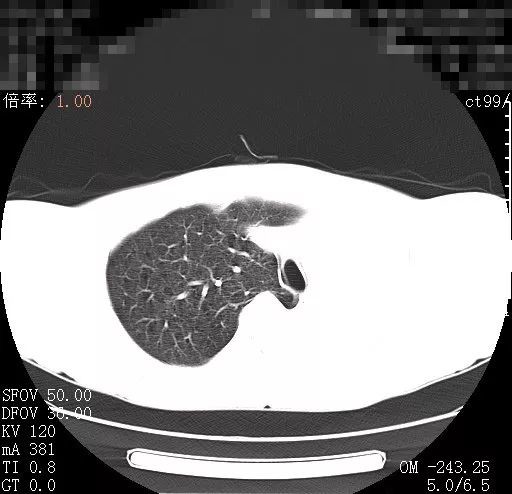

![中医治疗#肺癌# ,是如何一步一步好转的?【门诊案例,仅供参考,不可一概而论,如有问题,须由专业医生问诊之后开方】郑女士 62岁 农民 患者在地里干活时出现胸背部疼痛剧烈,咳嗽,咳痰就赶紧去当地医院就诊行胸椎MRI显示:1.T5/6椎体及其右侧椎弓根异常信号;2.左侧胸腔积液。胸部CT显示:1.左肺门旁占位病变2.纵膈淋巴结多发转移2.双侧胸腔积液3.T5椎体右侧横突、椎弓根及第5、6后肋骨转移。考虑为肺癌骨转移在CT引导下行经皮左肺占位穿刺活检术,术后病理确诊为左肺腺癌。基因检测示:EGFR L858R 突变丰度27%,21因子突变。最终确诊为左肺腺癌;纵膈淋巴结转移,胸腔转移,多发骨转移做了放化疗和吃靶向药之后,患者身体承受不住,当地医院建议,找个好一点的中医调理一下,患者经过病友推荐,找到了我。【症状表现】胸背疼痛,咳嗽,痰少,喘促,痰中带血,乏力气短,面色苍白,纳差,舌淡红,有齿痕,舌苔白,脉细弱。【诊断结果】毒邪蕴结 气血虚弱证【诊治思路】益气补血,解毒抗癌经我开的方子调理之后,患者身体明显好转,胸腰背疼痛,咳嗽,痰中带血,症状消失。复查结果显示患者肺内、纵隔肿瘤,胸腔积液已经基本消失,各项指标均恢复正常,达到临床治愈。目前继续中医药并靶向治疗防止复发。郑女士的身体非常好,已与正常人无异,这样的结果让患者及家属都非常满意,开玩笑说要不是当初的这些片子,病理报告,甚至有些怀疑当初是误诊了呢![你好]我是肿瘤科医生武常生,擅长用中医的方法治疗肺结节、乳腺结节、甲状腺结节、肺癌、乳腺癌、肠癌、宫颈癌、卵巢癌等肿瘤结节问题,并且有多年的临床治疗经验【如果你有肺结节、乳腺结节、甲状腺结节、肺癌、乳腺癌、肠癌、宫颈癌、卵巢癌等结节肿瘤方面的问题,需要我的帮助,可以在评论区打“需要帮助”,帮你辨证分析】](https://wx2.sinaimg.cn/large/008oAFzaly1hlsytz68n3j30b407qdjd.jpg)

中医治疗#肺癌# ,是如何一步一步好转的?【门诊案例,仅供参考,不可一概而论,如有问题,须由专业医生问诊之后开方】郑女士 62岁 农民 患者在地里干活时出现胸背部疼痛剧烈,咳嗽,咳痰就赶紧去当地医院就诊行胸椎MRI显示:1.T5/6椎体及其右侧椎弓根异常信号;2.左侧胸腔积液。胸部CT显示:1.左肺门旁占位病变2.纵膈淋巴结多发转移2.双侧胸腔积液3.T5椎体右侧横突、椎弓根及第5、6后肋骨转移。考虑为肺癌骨转移在CT引导下行经皮左肺占位穿刺活检术,术后病理确诊为左肺腺癌。基因检测示:EGFR L858R 突变丰度27%,21因子突变。最终确诊为左肺腺癌;纵膈淋巴结转移,胸腔转移,多发骨转移做了放化疗和吃靶向药之后,患者身体承受不住,当地医院建议,找个好一点的中医调理一下,患者经过病友推荐,找到了我。【症状表现】胸背疼痛,咳嗽,痰少,喘促,痰中带血,乏力气短,面色苍白,纳差,舌淡红,有齿痕,舌苔白,脉细弱。【诊断结果】毒邪蕴结 气血虚弱证【诊治思路】益气补血,解毒抗癌经我开的方子调理之后,患者身体明显好转,胸腰背疼痛,咳嗽,痰中带血,症状消失。复查结果显示患者肺内、纵隔肿瘤,胸腔积液已经基本消失,各项指标均恢复正常,达到临床治愈。目前继续中医药并靶向治疗防止复发。郑女士的身体非常好,已与正常人无异,这样的结果让患者及家属都非常满意,开玩笑说要不是当初的这些片子,病理报告,甚至有些怀疑当初是误诊了呢![你好]我是肿瘤科医生武常生,擅长用中医的方法治疗肺结节、乳腺结节、甲状腺结节、肺癌、乳腺癌、肠癌、宫颈癌、卵巢癌等肿瘤结节问题,并且有多年的临床治疗经验【如果你有肺结节、乳腺结节、甲状腺结节、肺癌、乳腺癌、肠癌、宫颈癌、卵巢癌等结节肿瘤方面的问题,需要我的帮助,可以在评论区打“需要帮助”,帮你辨证分析】